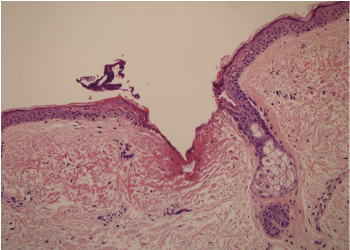

放大皮膚切片圖100倍後能清晰看到療程後表皮即時形成微創傷口。

療程後即時

病人MZ: 能量80%---皮膚顯示燒焦灶,直徑為0.26毫米,穿透深度: 0.55毫米

病人MZ

皮膚顯示燒焦灶,

直徑為0.26毫米 穿透深度: 0.55毫米